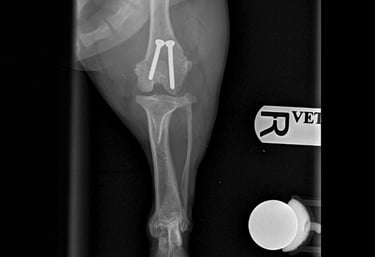

Orthopaedic surgery

Complete Surgical Equipment Package: All necessary orthopaedic equipment, power tools, and implants are brought to your clinic.

Follow-up Care: Aftercare service, ongoing management, and follow-up X-rays assessment as necessary.

The following images and case studies are intended for veterinary professionals and may include explicit surgical content, such as blood, anatomical structures, and medical procedures. These materials could be distressing to some viewers.

By clicking on the following images, you will be redirected to a new page with detailed clinical cases. Viewer discretion is advised!